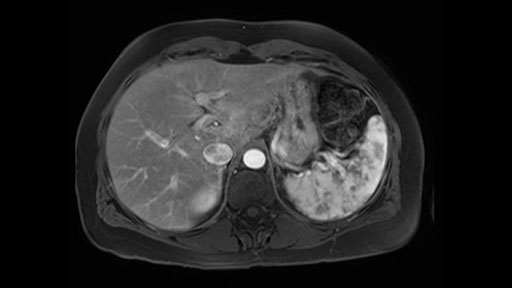

In reviewing this patient’s CT scan, first of all, the lesion is again cystic with a very thin wall. I anticipate that it will be delicate and potentially friable. And therefore the risk of rupture exists and we need to be very careful in how we handle the pancreas and the tumor throughout the procedure.

The preoperative MR is very very important; any scan for that matter. Whether it is a pancreatic protocol CT scan or the MR as presented, the diagnostic imaging plays a very big role. And with this we see that it’s a very well-defined cystic focus in the body of the pancreas. Although there are septal enhancements, very well demarcated, but there is no vascular involvement. However, the mass appears to be in contact with the splenic vessel, and the mass is also a little bit in touch with the left adrenal and also the loop of bowel. So looking at this, basing on the features, I think it’s probably a mucinous cystic lesion, it could possibly be a pseudocyst. But basing on the history, it appears like there is no history that would point out to a pseudocyst. And not an IPMN as well; I don’t see any side branches from the MRCP and the MR scan and although there is no axial T2 images available, and I truly find it easier to identify the septations on T2, and the hepatic cyst that is visible on this scan makes it hard to differentiate it from a simple or complex cyst which may be considered in a mucinous neoplasm with cystic or mucinous metastasis. Basically the contrast would help us in identifying the enhancing mural nodules or septations in the cysts. The MRCP is definitely helpful to identify if there is any side branch, if we are considering any IPMN.

So first, I'll show you the scan. Here's the traditional view, where you see the cyst, which is in the body of the pancreas. And you see over here, it's got a quite thick wall. And going a little bit back also, here you see a septation which is very important, because I think a septation is what separates this from, for instance, the pseudocyst of the pancreatitis. And also the location of the cyst you see here, abutting the adrenal gland and going down a bit more, it's also quite close to a bowel loop. So when thinking about this cyst: female, the location in the body of the pancreas, thick wall, septation, and as you can read in history, it was basically asymptomatic, so no signs of pancreatitis. So, this probably all points towards a mucinous cystic neoplasm.